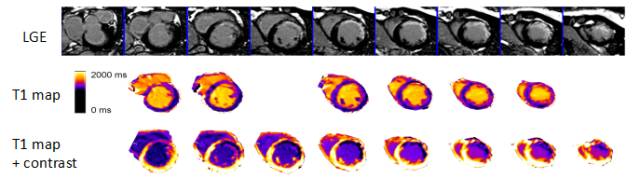

心脏核磁共振成像(MRI)

◆具有大视野、任意角度、良好的空间分辨力、高度的组织定性及没有离子辐射暴露等特点,是评价心室容积、功能及室壁运动的“金标准”。

◆对比剂(钆)增强的心肌灌注扫描及延迟强化(Late Gadolinium Enhancement, LGE),可用于评价心肌缺血、识别存活心肌、诊断心肌瘢痕或纤维化。